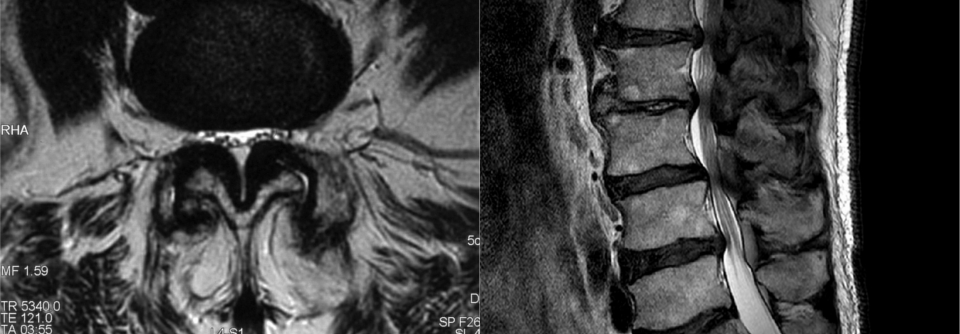

Wann sollte die lumbale Spinalkanalstenose operativ behandelt werden?

Die lumbale Spinalkanalstenose ist der häufigste Grund für operative Eingriffe an der Wirbelsäule von über 60-Jährigen. Die Erfolgsaussichten sind…